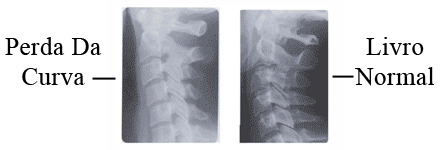

Um resultado comum de aceleração / desaceleração lesões é a perda da curva normal para a frente, causando a quiropraxia, ortopédicas ou neurológicas achado de exame.